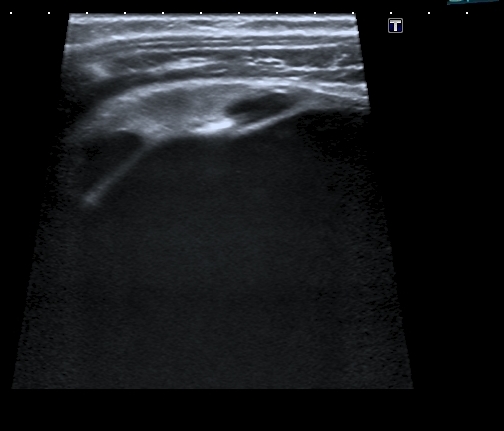

Тему уже давно закрыли, но вот свежая "красивая" картинка; левая почка незначительно увеличена в размерах, без изменений ЧЛС, со слов больного он уже несколько лет наблюдается у уролога: